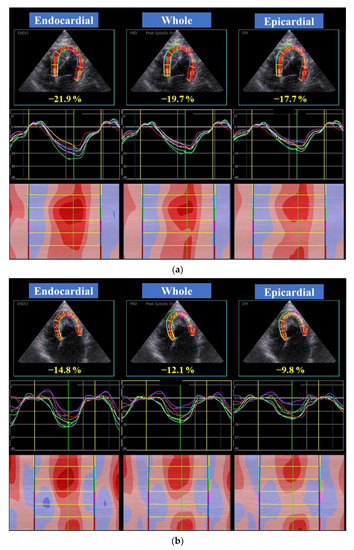

| Global RV longitudinal strain (%) | |||||||

| Whole layer | 22.9 | (16.4, 31.9) | 10 | 31.6 | (27.8, 39.1) | 15 | 0.07 |

| Endocardial layer | 24.9 | (19.0, 34.2) | 10 | 34.8 | (29.6, 42.3) | 15 | 0.10 |

| Epicardial layer | 21.3 | (14.0, 29.8) | 10 | 29.0 | (26.0, 36.4) | 15 | 0.045 |

| Endo/Epi | 1.21 | (1.13, 1.30) | 10 | 1.15 | (1.13, 1.18) | 15 | 0.03 |